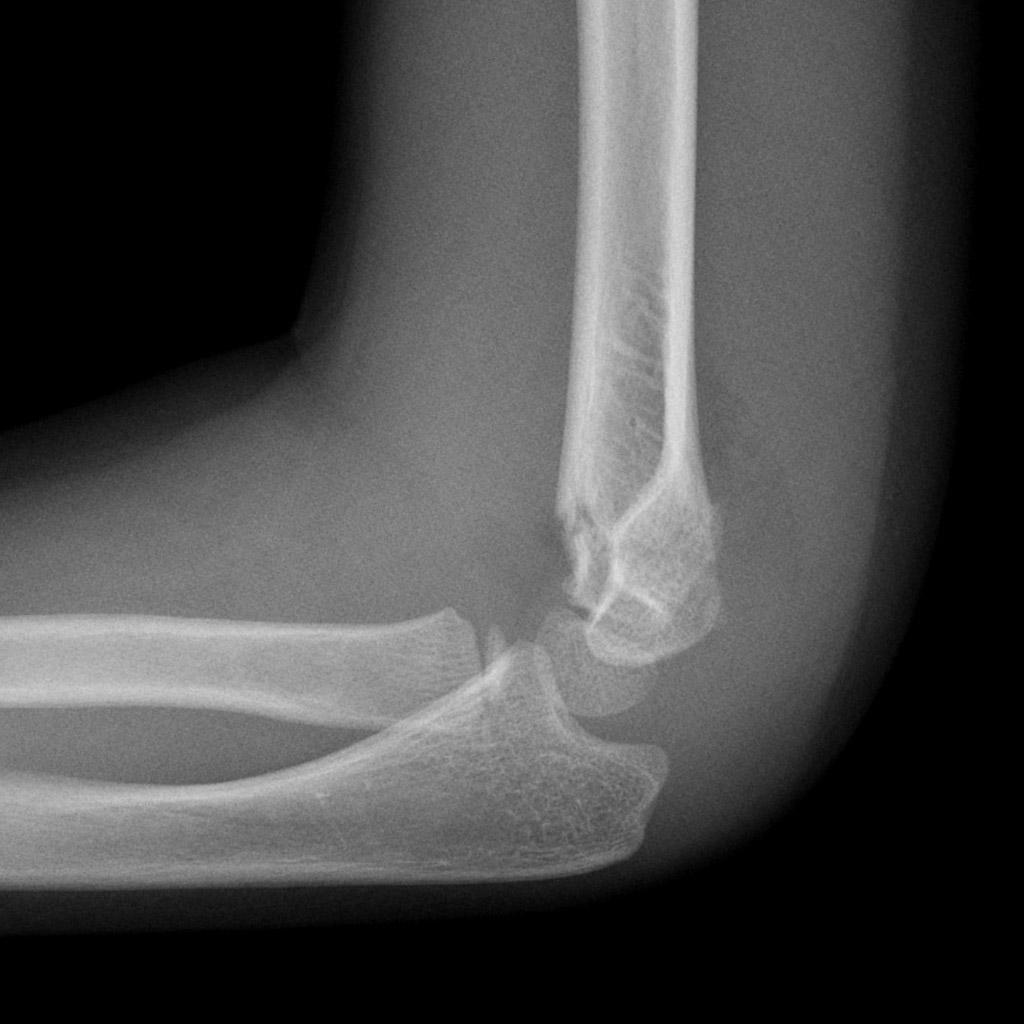

Sometimes no obvious fracture line for a supracondylar fracture can be identified. What should you look for instead?

What injury can be seen?

Supracondylar fracture

What is the posterior fat pad sign?

a lucent crescent of fat located in the olecranon fossa on a true lateral view of an elbow joint with the elbow flexed at a right angle

What does a posterior fat pad sign indicate? What should you look for in adults? In children?

Indicates an elbow joint effusion that suggests a non-displaced fracture

In adults: radial head fracture

In children: supracondylar fracture